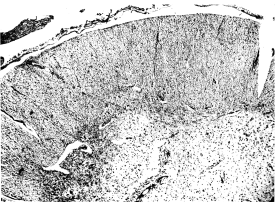

| 3. | Lumbar cord in case of scurvy | 105 |

| 4. | Lumbar cord in case of scurvy. Focal degeneration | 105 |